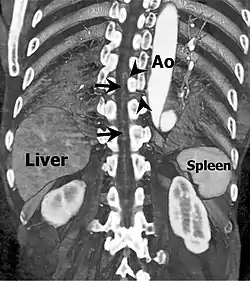

Coronal slab volume rendering image of CT aortography shows artery of Adamkiewicz entering spinal canal(arrowheads) and joining the anterior spinal artery (arrows) after a hairpin turn.

In human anatomy, the artery of Adamkiewicz (also arteria radicularis magna) is the largest anterior segmental medullary artery.[3] It typically arises from a left posterior intercostal artery at the level of the 9th to 12th intercostal artery, which branches from the aorta, and supplies the lower two-thirds of the spinal cord via the anterior spinal artery.[4]

It is important to identify the location of the artery when surgically treating an aortic aneurysm to prevent damage which would result in insufficient blood supply to the spinal cord.[14] In bronchial artery embolization for treatment of massive hemoptysis, one of the most serious complications is inadvertent occlusion of the artery of Adamkiewicz.[15] Its location can be identified with computed tomographic angiography.[16]